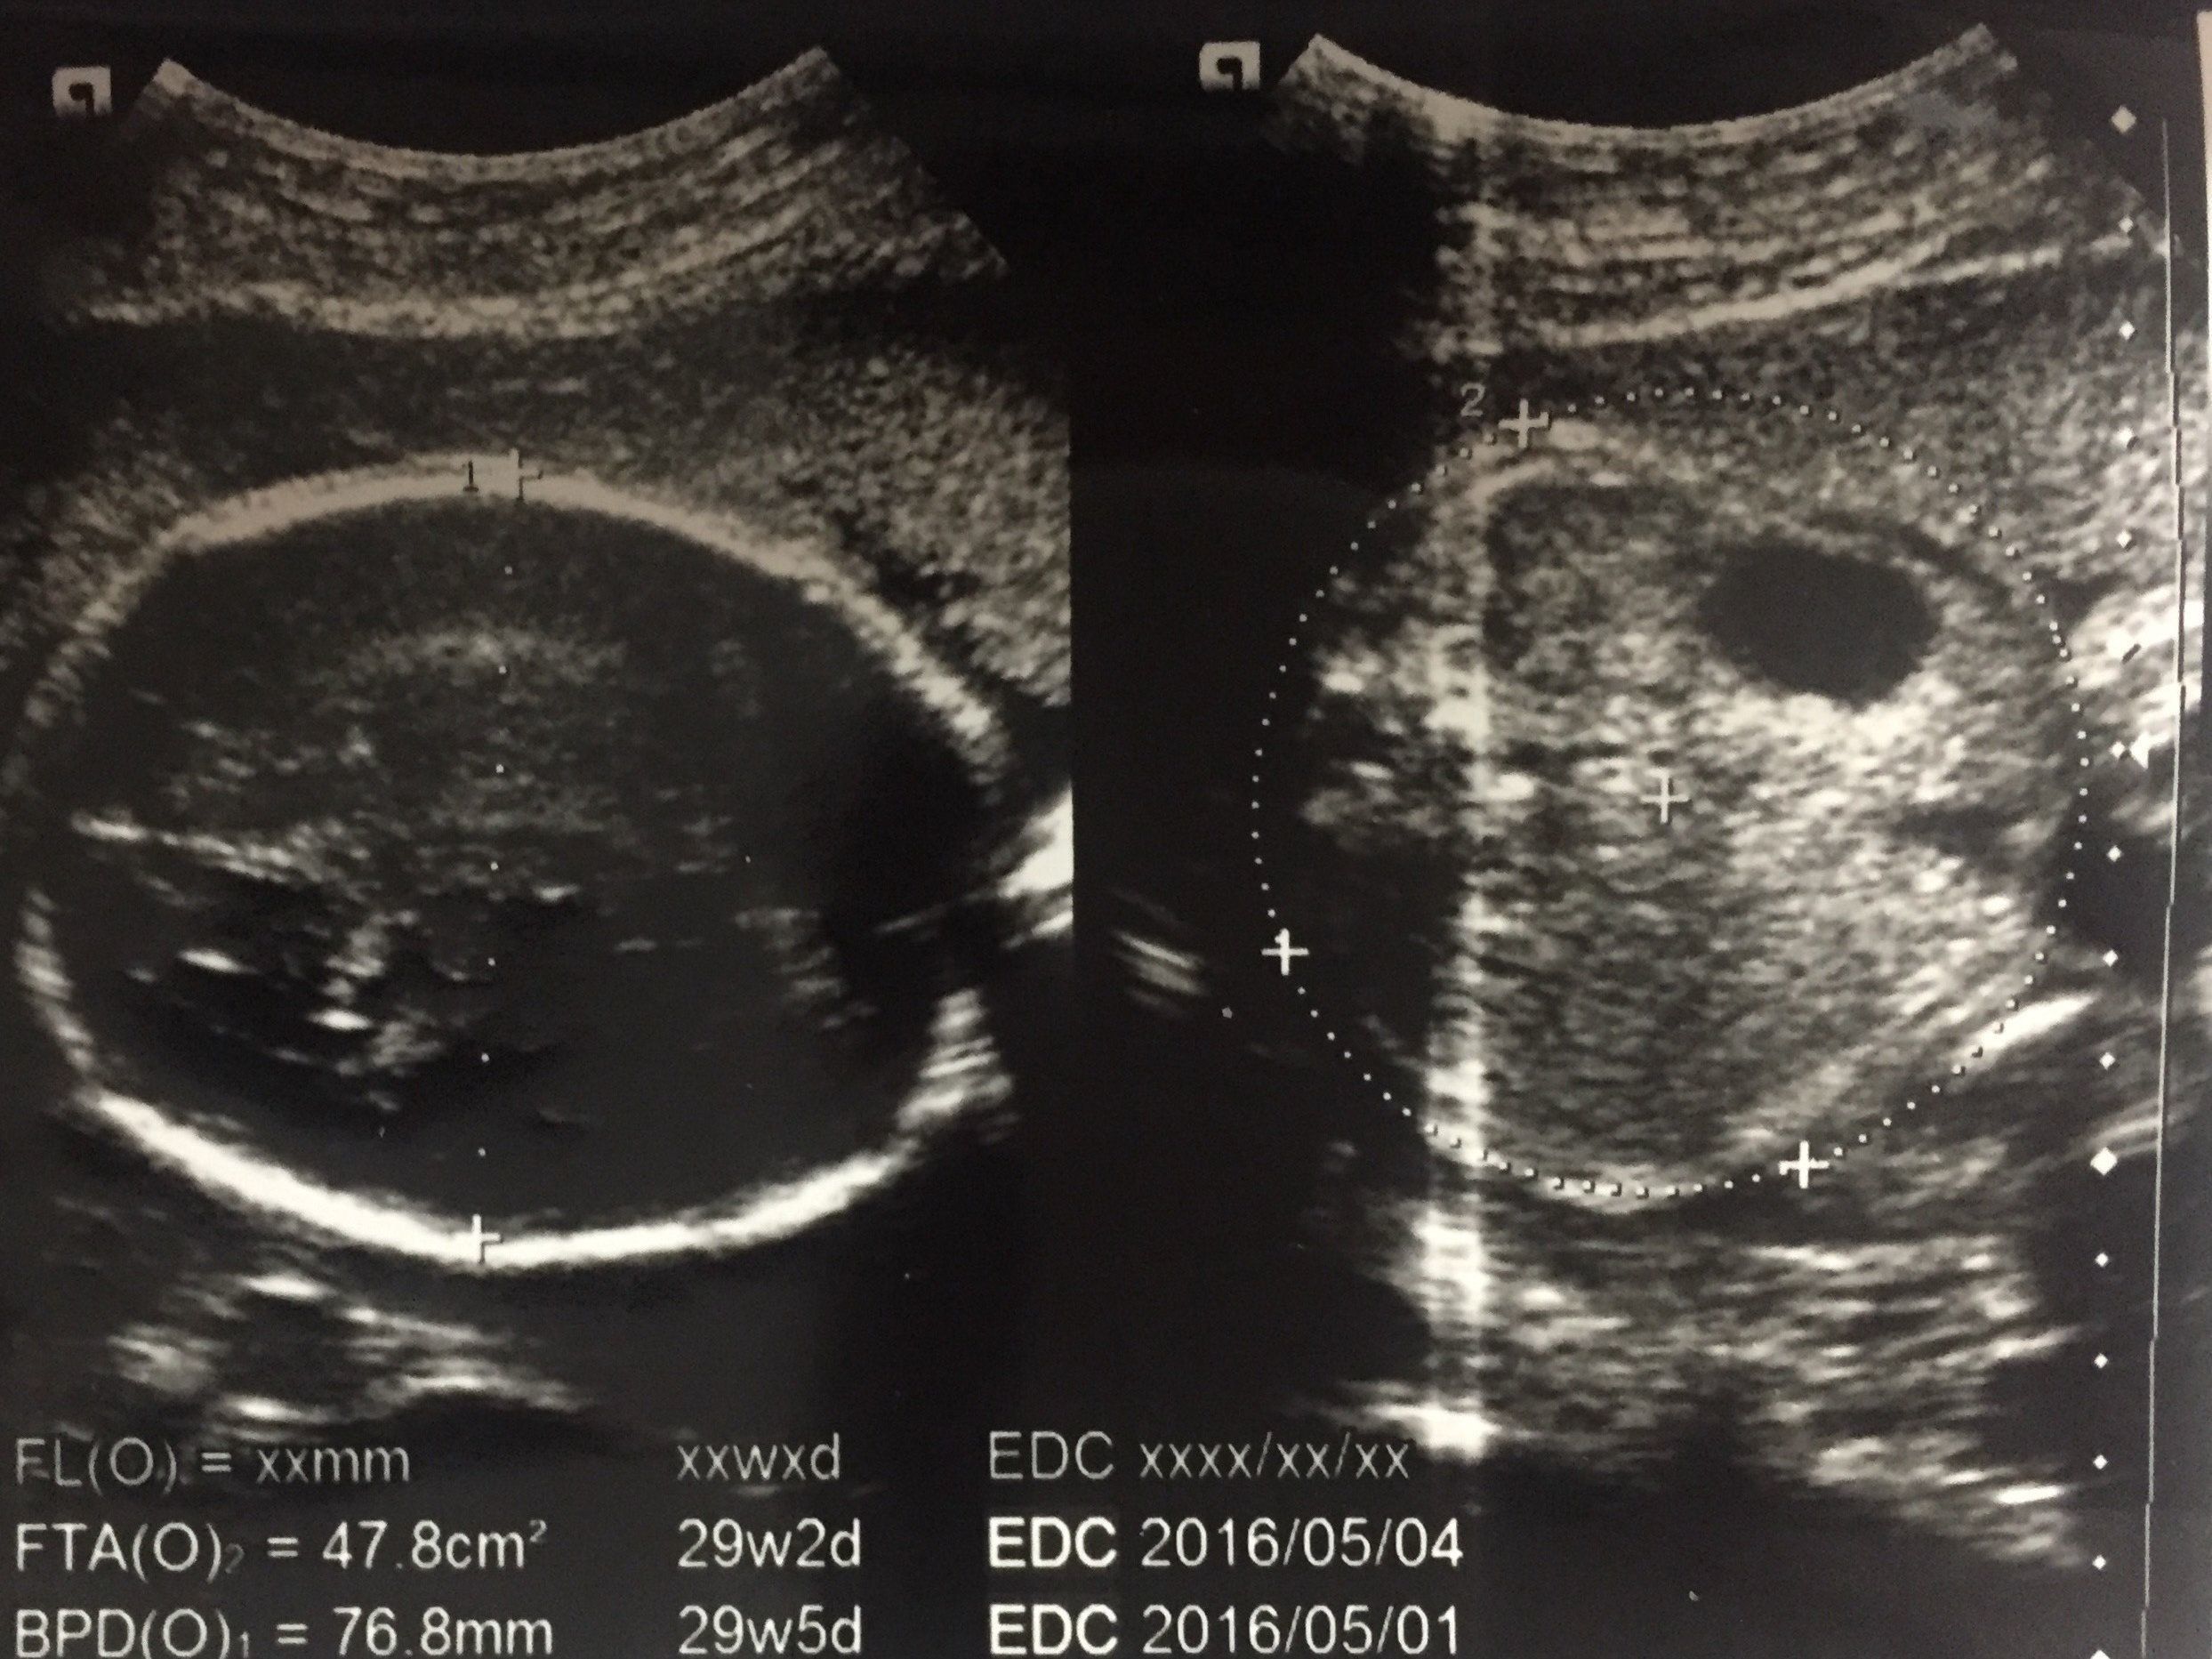

妊娠29週目 逆子で帝王切開の可能性も視野に

赤ちゃんの頭を上から撮影したものです。妊娠20週あたりから健診の度に「逆子だけど、そのうち回転するかもしれない」と言われてきました。それほど気にしていなかったのですが、そのまま妊娠後期に入ったので「このままだと帝王切開になるのだろうか」と考え始めました。

普通分娩の強い希望があったわけでもなかったので、冷静に帝王切開について調べて心の準備をしていました。